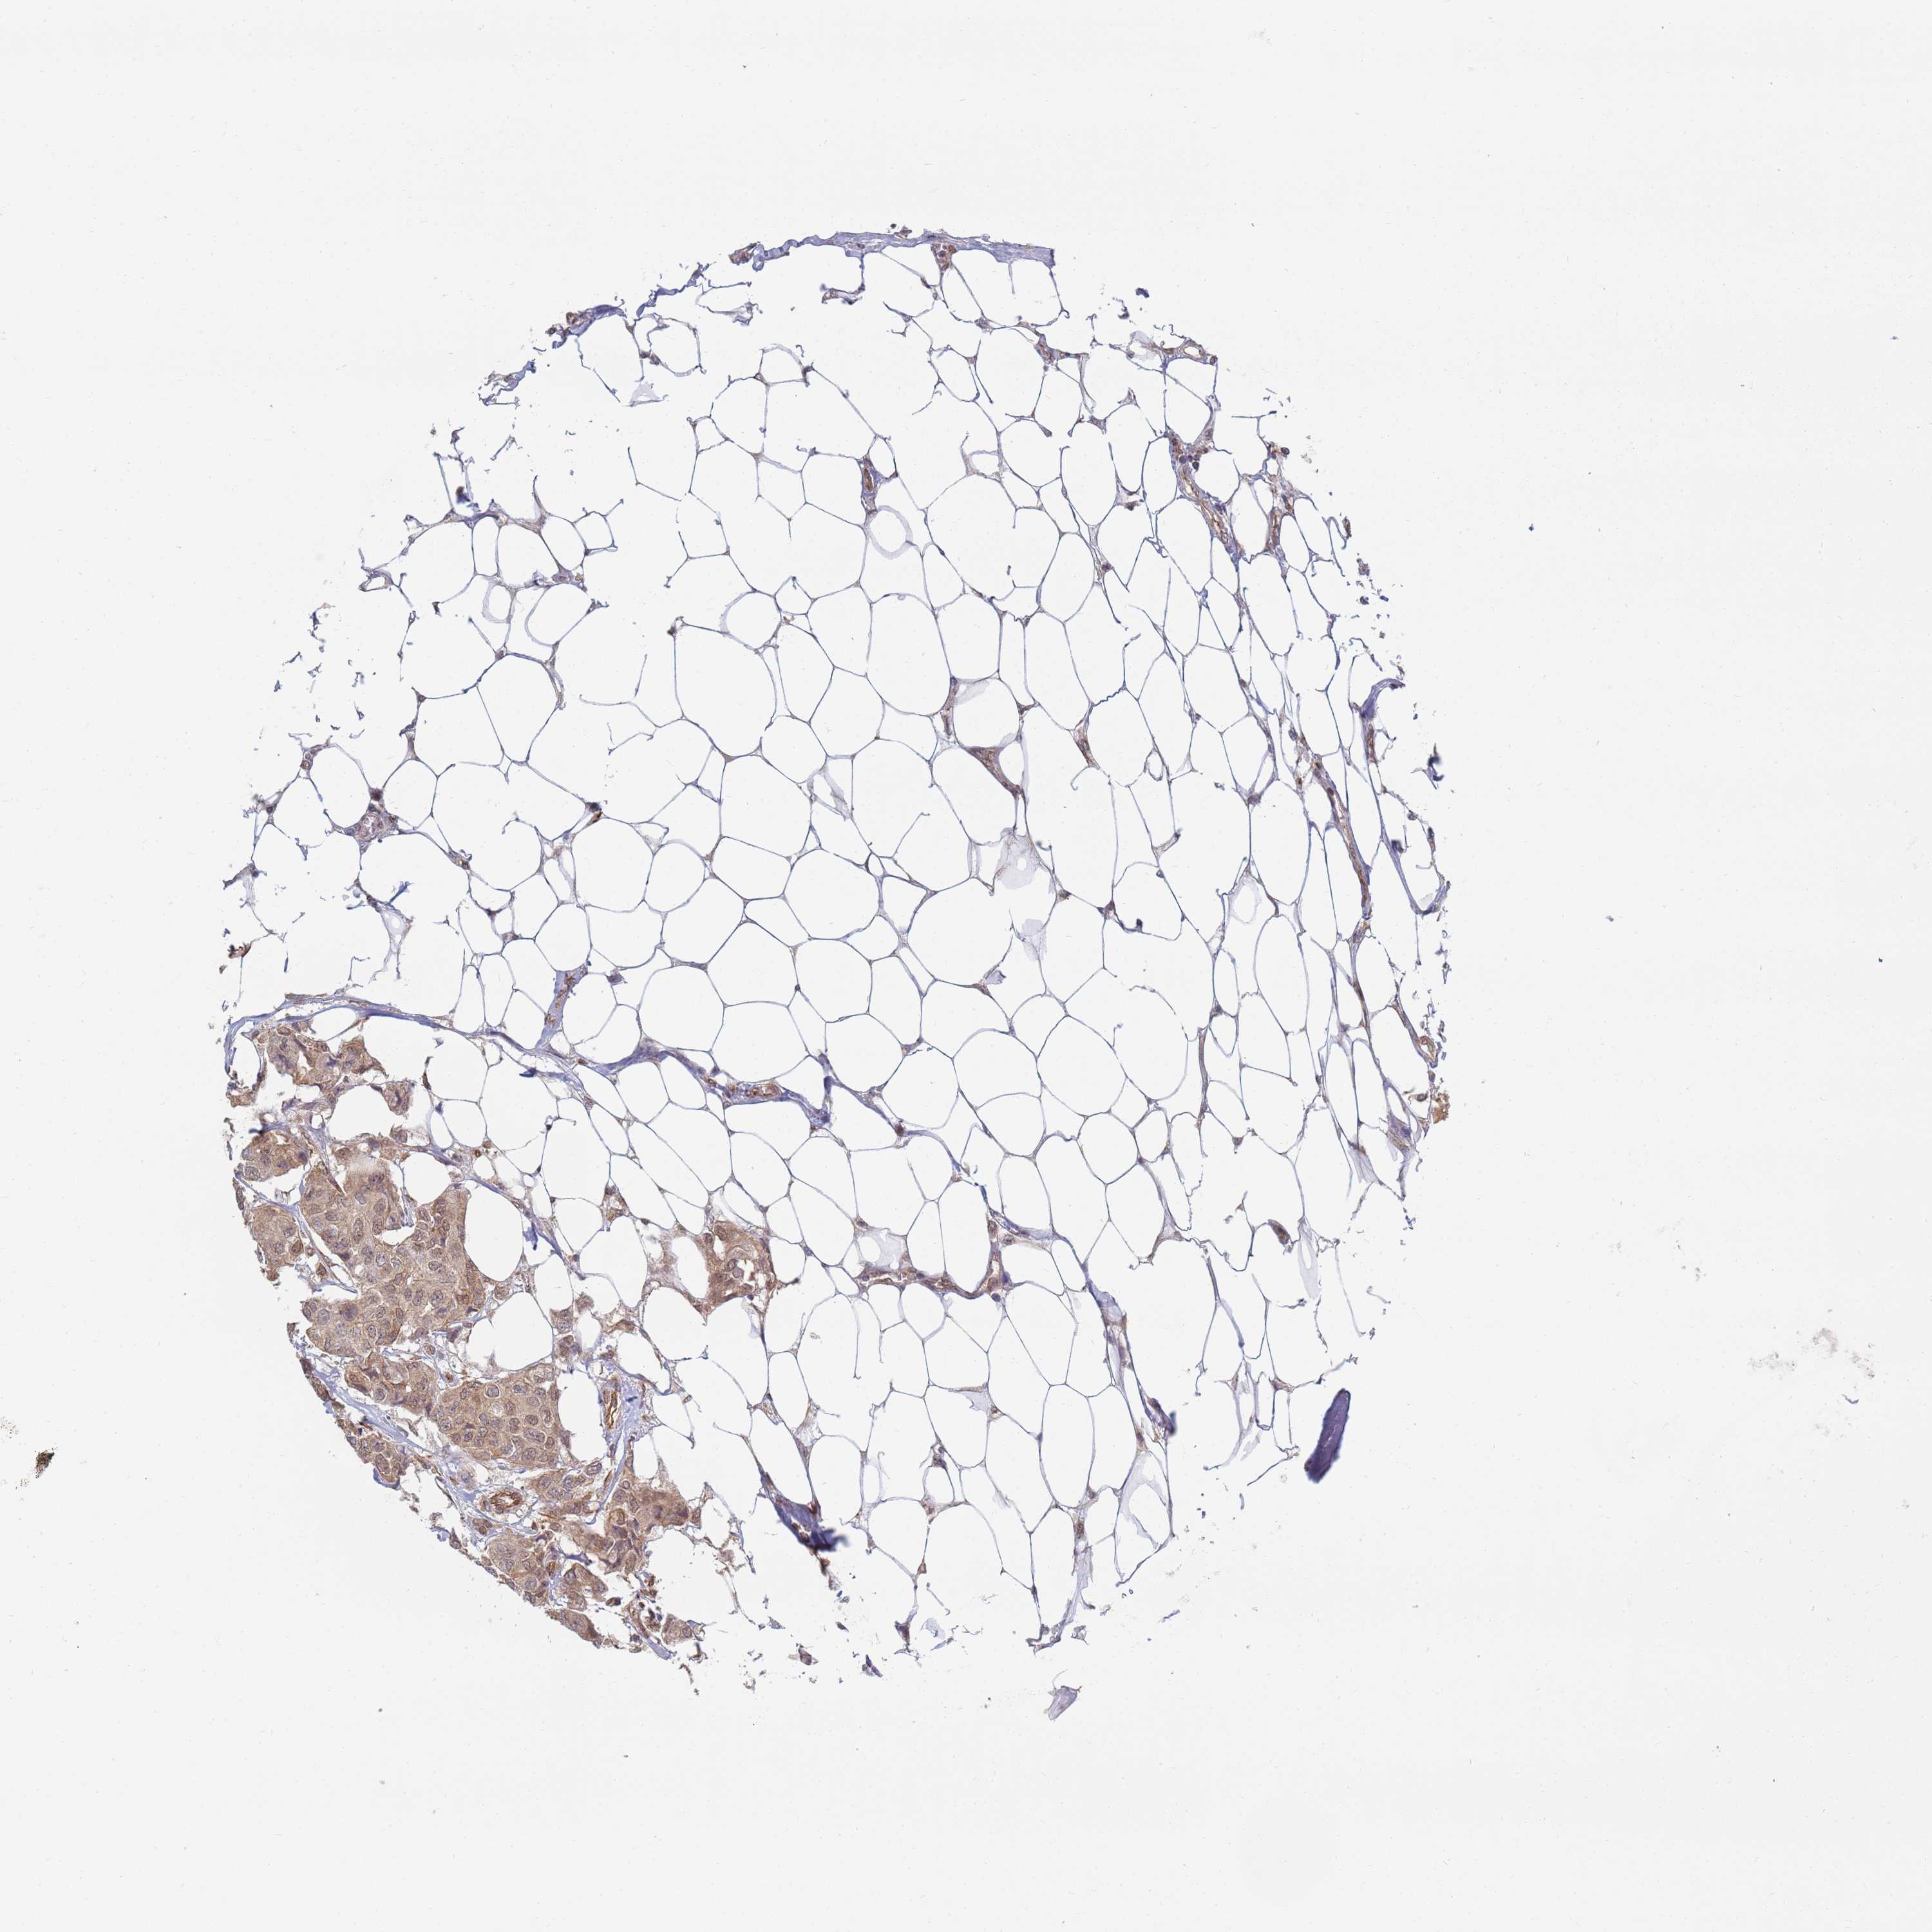

CANCER BREAST CANCER Show tissue menu

BRCA TCGA BRCA VALIDATION PROTEIN EXPRESSION

ANTIBODIES

AND

VALIDATION